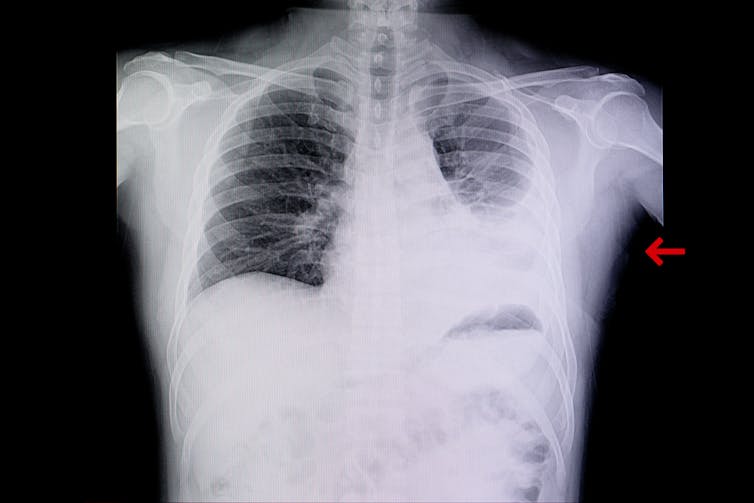

Pneumonia is inflammation of the lungs, usually caused by bacterial or viral infections. It may affect deeper lung tissues than bronchitis, which is airway tube inflammation, and can have symptoms such as fever, breathing problems and chest pain, showing up as a white shade in lung chest X-rays. There is no special designation of “white lung pneumonia”, scary as it may sound.